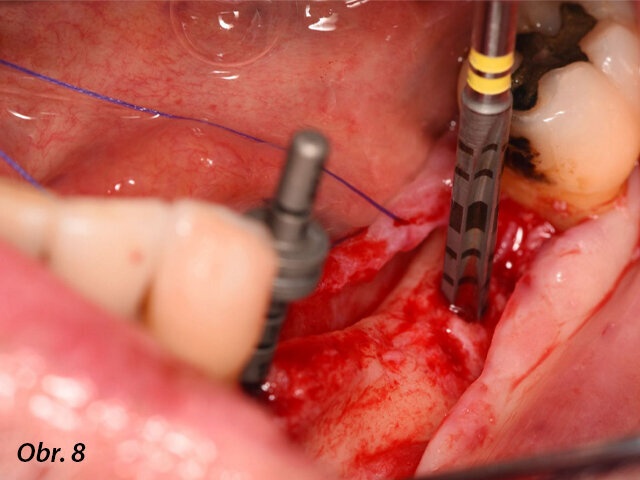

Meziodistálně byl implantát umístěn nejméně 1,5 mm od sousedního přirozeného zubu a mezi dvěma implantáty byla zachována vzdálenost 3,0 mm. Lůžka implantátů byla preparována podle pokynů výrobce a každý vrtáček byl použit za hojné irigace. Za účelem správné prostorové pozice implantátů byly použity paralelizační piny (obr. 8–10).